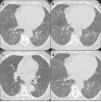

After a month, a new chest HRCT showed a significant improvement in the lung parenchymal involvement and the respiratory failure was resolved (Fig. 2). Finally, mycophenolate mofetil (MMF) was added to the treatment as steroid-sparing and maintenance drug.